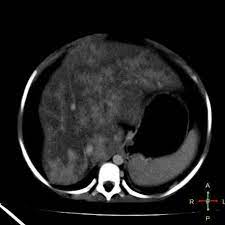

Chiasmata -mə-tə or chiasmas also chiasms 1. Esophageal varices are extremely dilated sub-mucosal veins in the lower third of the esophagus. Located in metro Denver northern Colorado and western Nebraska serving all of the Front Range our team consists of board-certified and fellowship-trained interventional radiologists. This results in hepatic congestion similar to Budd-Chiari syndrome and post-sinusoidal portal hypertension. The patients condition should be monitored throughout the procedure. They are most often a consequence of portal hypertension commonly due to cirrhosis. Toxic injury to liver sinusoids causes sloughing of endothelial cells that embolize to hepatic venules and cause eventual fibrosis of the venules. Coin in the Esophagus. There is no clear consensus regarding the number of occluded veins some authors claim that there should be at least one occluded hepatic vein 7 others state that there are no significant.

Carcinoma of the Colon. Budd-Chiari syndrome a blockage in one or more veins that carry blood from the liver back to the heart. And coumarin skin necrosis adrenal gland hemorrhage and infarction. Toxic injury to liver sinusoids causes sloughing of endothelial cells that embolize to hepatic venules and cause eventual fibrosis of the venules. Chiari malformation CM is a structural defect in the cerebellum characterized by a downward displacement of one or both cerebellar tonsils through the foramen magnum the opening at the base of the skull. Embolism and thrombosis of. La présence dune ou plusieurs affections prothrombotiques est fréquente La prise en charge repose sur un traitement anticoagulant précoce le traitement de l.